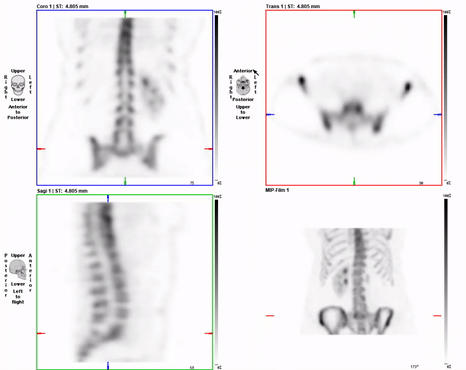

Bone – SPECT

• Various displays and MIP presentation